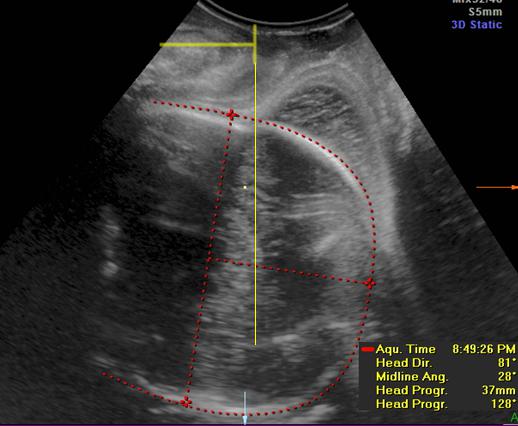

GE公司的SonoVCAD labor技术是基于三维容积超声的计算机辅助产程监测软件。利用三维超声多平面成像技术,可同时显示相交平面,增加了更多信息,使得测量的切面更为准确,重复性佳[5]。软件可在三维容积数据的不同平面自动测量出相应的胎头方向角(图1)、胎头进展角(图2)、胎头下降距离(图3)及中线角(图4)这四个参数,并在产程中动态观察各参数的变化,利用软件记录产程的全过程(图5),从而监测第二产程进展。

图1.在 A 平面, 描记胎头最大经线,从胎头中间点向外拉线,十字交叉点落在胎头轮廓的最远点,并与胎头最大经线垂直。胎头方向角就是耻骨联合下缘垂线和与胎儿颅脑最宽径的垂直线的夹角。